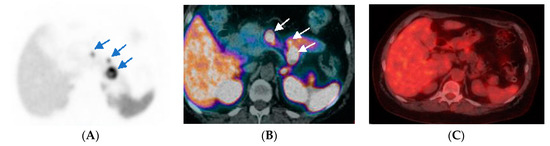

- Chan, D.L.; Pavlakis, N.; Schembri, G.P.; Bernard, E.J.; Hsiao, E.; Hayes, A.; Barnes, T.; Diakos, C.; Khasraw, M.; Samra, J.; et al. Dual somatostatin receptor/FDG PET/CT Imaging in metastatic neuroendocrine tumours: Proposal for a novel grading scheme with prognostic significance. Theranostics 2017, 7, 1149–1158. [Google Scholar] [CrossRef] [PubMed]

- Hindié, E. The NETPET Score: Combining FDG and Somatostatin Receptor Imaging for Optimal Management of Patients with Metastatic Well-Differentiated Neuroendocrine Tumors. Theranostics 2017, 7, 1159–1163. [Google Scholar] [CrossRef] [PubMed]

- Karfis, I.; Marin, G.; Levillain, H.; Drisis, S.; Muteganya, R.; Critchi, G.; Taraji-Schiltz, L.; Guix, C.A.; Shaza, L.; Elbachiri, M.; et al. Prognostic value of a three-scale grading system based on combining molecular imaging with 68Ga-DOTATATE and 18F-FDG PET/CT in patients with metastatic gastroenteropancreatic neuroendocrine neoplasias. Oncotarget 2020, 11, 589–599. [Google Scholar] [CrossRef]